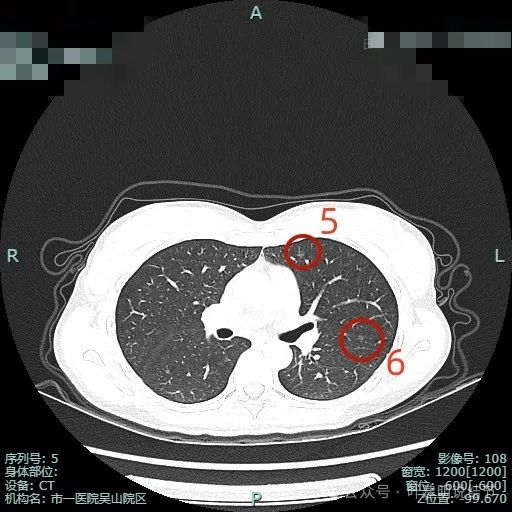

病灶5:左上叶淡磨玻璃结节,整体轮廓较清,有微小血管进入,考虑肺泡上皮增生或不典型增生可能。

病灶6:左上叶近斜裂处淡磨玻璃结节,整体轮廓较清,考虑肺泡上皮增生或不典型增生可能。